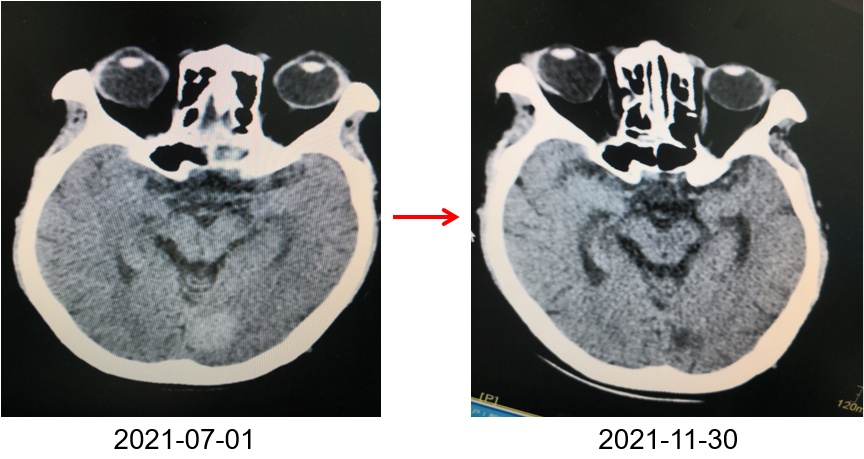

为提升肺癌前线免疫联合抗血管治疗的诊疗观念,学习与追踪肺癌领域诊疗最前沿知识,充分交流免疫/抗血管用药不良反应管理临床经验,【An例说】肺癌病例项目,征集大量临床高质量免疫联合抗血管治疗肺癌病例,并邀请全国各区域中青年及高职称医生与顶级TOP KOL互动发声!通过理念结合实践,研究结合病例,线上联动,共同促进学术由KOL/ROL向中青年医生下沉,为提升我国肺癌诊疗整体水平势在必行。免疫治疗的出现,特别是以PD-1/PD-L1为代表的免疫检查点治疗的出现,对于转移性的晚期肺癌患者而言,给患者增加了更多治疗的选择,同时,多项临床研究表明免疫治疗显著延长了患者的生存期及生活质量。为此,河北北方学院附属第一医院为您带来一例“双安疗法”用于二线治疗小细胞肺癌病例的治疗分享。 案例详情 基本情况 患者,霍xx,女,60岁。 初治时间:2020-10-16 既往史:COPD 4年,间断口服茶碱治疗,否认其他慢性病史及传染病史。否认过敏史。 个人史:无特殊 家族史:无特殊 ADL评分:90分;Khorana评分1分 入院初步检查结果 体格检查: COPD 4年,间断口服茶碱治疗,否认其他慢性病史及传染病史。否认过敏史。 个人史、婚育史、家族史无特殊。 辅助检查 血常规、肝肾功、凝血功能无明显异常。 肿瘤标志物(特异性+异常指标)。 肿瘤标志物变化趋势 NSE(神经元特异性烯醇化酶)变化趋势: NSE变化趋势 基线情况: 2020-10-16,患者无明显诱因出现咳嗽、咳痰,偶有痰中带血,伴胸闷气短4个月于我院就诊:查胸部CT:胸廓左侧塌陷,左肺上叶尖后段及下叶支气管截断,左肺下叶见软组织密度团块。右肺中叶容积小。左主支气管内见高密度影,纵隔多发肿大的淋巴结,胸膜厚,左侧少量胸膜腔积液。 浅表淋巴超声、全身骨扫描等检查提示肺外脏器未见异常。 肺部CT提示左肺占位伴阻塞性肺炎、纵隔淋巴结肿大,左侧胸腔积液。 患者遂就诊于解放军81集团军医院行支气管镜检查提示小细胞肺癌。 影像学检查 诊断结果 1.左肺小细胞肺癌(广泛期)伴胸膜转移、伴纵隔淋巴结转移 2.阻塞性肺炎 3.慢性阻塞性肺疾病 诊疗依据 (CSCO)小细胞肺癌诊疗指南2020 05治疗经过 第一阶段治疗: 胸部CT对比:较前片(2020-10-16)对比:左肺上叶复张且高密度影明显吸收;左肺占位及纵隔淋巴变化不明显,左侧胸腔积液基本吸收。 胸部CT检查对比 胸部CT对比:较前片(2020-11-26)对比:左肺占位变化不明显;纵隔部分淋巴结增大。 胸部CT检查对比 胸部CT对比:较前片(2020-12-30)对比,左肺占位明显增大,隔巴结增大,左侧胸腔新发积液,左肺上叶膨胀不全,左肺上叶新发片状高密度影。 胸部CT检查对比 胸部CT对比:较前片(2021-03-02),左肺占位性病变较前增大,纵膈肿木淋巴结较前增大。 胸部CT检查对比 胸部CT对比:较前片(2021-04-04)左肺中心型肺Ca伴左肺不张,较前增大。右肺中叶不张。纵隔多发肿大融合淋巴结,部分包绕上腔静脉,较前增大。心包少量积液、主肺动脉干增粗。左侧胸腔积液(±)。 胸部CT检查对比 头颅CT对比:2021-06-21头颅CT:考虑左枕叶、右颞叶转移瘤。尾状叶头密度增高。 头颅CT检查对比 腹部CT:较前片(2021-04-04)左肾上腺增粗,考虑转移瘤? 腹部CT检查对比 第二阶段治疗:免疫+安罗替尼。ADL评分:70分;Khorana评分3分。 胸部CT对比:对比前片(2021-06-21),左肺占位减小,纵隔部分淋巴结减小,胸腔积液吸收。 胸部CT检查对比 头颅CT对比:对比前片(2021-06-21):颅内占位变化不著。 头颅CT检查对比 胸部CT对比:对比前片(2021-07-27):左肺占位减小,纵隔部分淋巴结减小;左肺上叶片状高密度影略显吸收。 胸部CT检查对比 胸部CT对比:对比前片(2021-8-23):左肺占位及纵隔淋巴结有所减小。 胸部CT检查对比 胸部CT对比:对比前片(2021-10-29):左肺占位及纵隔淋巴结变化不著。 胸部CT检查对比 头颅CT对比:较前片(2021-07-01)对比:左枕叶、右颞叶占位明显减小。 头颅CT检查对比 胸部CT对比:对比前片(2021-11-30):左肺占位及纵隔淋巴结变化不著,腹部较前变化不著。 胸部CT检查对比 目前情况:患者神清,精神尚可,无咳嗽咳痰,偶有喘憋气短,饮食睡眠尚可,二便正常。 面部及双手皮疹样改变。 目前诊断: 1. 左肺小细胞肺癌(广泛期)伴胸膜转移、伴纵隔淋巴结转移、伴脑转移、伴肾上腺转移 2. 慢性阻塞性肺疾病 3. 下肢静脉血栓形成 4. 低钠血症 ADL评分:80分;Khorana评分2分 06病程回顾 专家点评 该病例,女性,无吸烟史,既往自2014年开始反复因咳嗽、咳痰、咯血于我院门诊或住院治疗,诊断为右中叶、双下肺基底段支气管扩张伴感染。2020年10月再次因咳嗽、咳痰、咯血行肺CT检查,检查结果示:支气管扩张、左下肺占位。后经支气管镜检查左下肺癌,病理为小细胞癌。结合肺CT:纵隔淋巴结肿大,左侧胸腔积液;临床诊断为:原发性支气管肺癌(左下广泛期小细胞肺癌)。PS评分1分,依据2020年CSCO小细胞肺癌指南Ⅰ级推荐选择化疗+免疫治疗,化疗方案:CE/EP,IC/IP,免疫治疗:atezolizumab。本病例中,患者因经济条件所限,未使用atezolizumab,化疗采用CE\EP\ZP一线及二线LE(共计7疗程),肺部病灶增大,左肺完全不张,脑转移,肾上腺转移,PS评分3分。再次依据CSCO指南,行颅脑放疗,采用PD-1(卡瑞丽珠单抗)+EP+安罗替尼(口服小分子多靶点抗血管生成药物)2个疗程后,肺部病灶明显缩小,颅内病灶消失,评效为PR;后因卡瑞丽珠单抗副作用:反应性皮肤毛细血管增生症(RCCEP)及手部皮肤皲裂,改换为派安普利单抗+EP+安罗替尼治疗,直至目前。左肺完全复张,病情明显改善,PS评分降至2分。 该患者全程治疗过程分析,单纯化疗疗效不显著,PD-1联合抗血管生成靶向药物后,使得患者病情控制,生存带来了希望。“双安”治疗方案副作用小,对PS评分高的患者也适用。派安普利单抗是唯一采用IgG1亚型且经FC段改造的新型PD-1单抗,副作用较国产其他IgG4亚型 PD-I更小;安罗替尼为口服小分子多靶点络氨酸酶抑制剂,靶点更加全面,疗效更优。采用“双安”治疗广泛期小细胞肺癌,本例虽为个例,但为临床医生提供了可践行的治疗方向,也期待着更多临床研究数据的公布,为小细胞肺癌的治疗提供强有力的治疗依据。 病例分享 王布 教授 河北北方学院附属第一医院呼吸科副主任医师,医学硕士 河北省中西医结合睡眠专业会委员 张家口市抗癌协会肺癌专业委员会委员 世界中医药学会联合会整合肿瘤专业委员会委员 在《Translational Cancer Research》、《Journal of biological regulators &homeostaticagents》、《中国临床药理学》、《中华结核与呼吸杂志》等杂志上发表学术论文10余篇,其中《川芎嗪联合顺铂影响Lewis肺癌小鼠移植瘤生长及微血管生成的研究》论文在2015年中国药学大会暨第十五届中国药师周上报告交流 荣获河北省科技进步三等奖1项,河北省医学会科技奖一等奖1项 目前以第一主研人主持河北省科技厅课题1项,市厅级课题2项 以第二主研人主持张家口市财政厅支持课题1项;河北省政府资助专科能力建设和专科带头人培养课题1项 获“河北省抗击新冠肺炎先进个人”、“河北省优秀共产党员”、“河北省冀青之星”、张家口市“最美科技工作者”,“张家口市抗击新冠肺炎先进个人”、“张家口市优秀共产党员”等荣誉称号。 专家点评 支学军 教授 河北北方附属第一医院主任医师 教授,河北北方学院硕士研究生导师 任河北省医学会内科学分会委员 张家口市医学会呼吸分会常务委员兼秘书 张家口市抗癌协会理事会理事 张家口市抗癌协会肿瘤临床化疗专业委员会常务委员 张家口市抗癌协会抗癌药物专业委员会常务委员等职务 从事呼吸科工作30余年,擅长肺部感染性疾病、肺癌、肺结核等疾病的诊治。